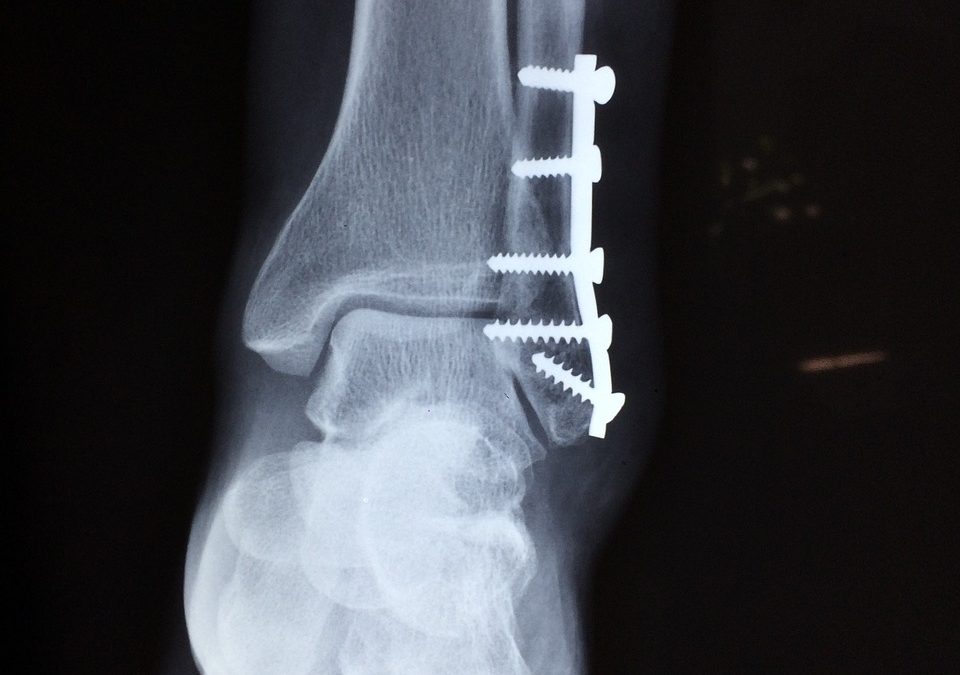

Multiple Ankle Sprains Leads To Poor Ankle Control Lateral ankle sprains are the most common ankle injury people suffer. Markelle Fultz suffered one during NBA summer league and did not play more games. Multiple sprains can result in chronic ankle stability issues....